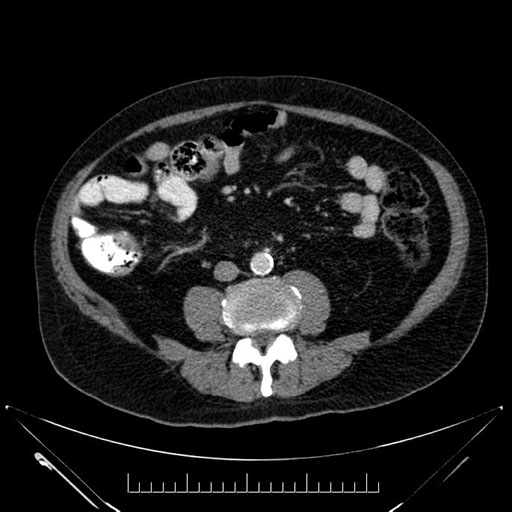

Imaging Analysis

Look through the patient's CT scan to identify any areas of concern for the necessary procedure.

Based on your CT findings, which issue(s) would give reason for "planned slowing down moment(s)" in this case?

Considering a standard Whipple procedure, what step(s) of the operation would you do differently in this case?